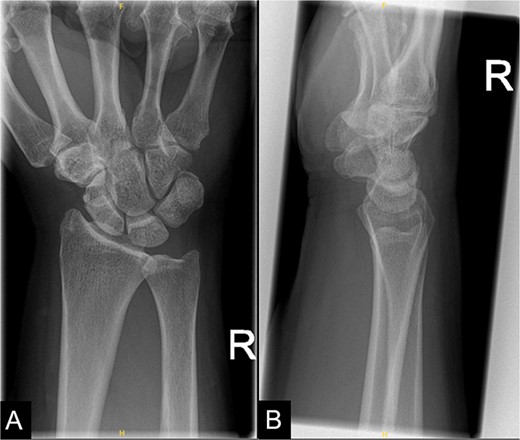

The patient was referred for hand therapy sessions and was prescribed non-steroidal anti-inflammatories to alleviate the pain. She was regularly being followed up in the clinic, where her symptoms had drastically improved after 4 months. A repeat X-ray of her right wrist showed that the previous calcific focus at the flexor carpi radialis tendon region had resolved following conservative management (Fig. 2).

A repeat X-ray of the right wrist indicating that the previous calcific focus at the flexor carpi radialis tendon region had resolved.